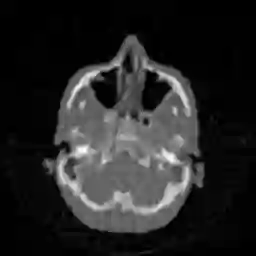

In this work, we propose Regularization-by-Equivariance (REV), a novel structure-adaptive regularization scheme for solving imaging inverse problems under incomplete measurements. Our regularization scheme utilizes the equivariant structure in the physics of the measurements -- which is prevalent in many inverse problems such as tomographic image reconstruction -- to mitigate the ill-poseness of the inverse problem. Our proposed scheme can be applied in a plug-and-play manner alongside with any classic first-order optimization algorithm such as the accelerated gradient descent/FISTA for simplicity and fast convergence. Our numerical experiments in sparse-view X-ray CT image reconstruction tasks demonstrate the effectiveness of our approach.